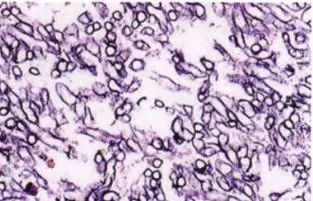

毛霉:无分隔的菌丝(分支呈直角)+ 孢子囊孢子。

上图是毛霉的病理图片。